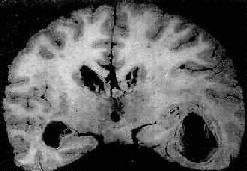

图16-11 化脓性脑膜炎 蛛网膜下腔充满脓性渗出物,血管扩张充血 【临床病理联系】 急性化脓性脑膜炎在临床上除了发热等感染性全身性症状外,常有一系列神经系统症状,表现为: (1)颅内压升高症状:头痛,喷射性呕吐,小儿前囟饱满等。这是由于脑血管充血,蛛网膜下腔渗出物堆积,蛛网膜颗粒因脓性渗出物阻塞而影响脑脊液吸收所致,如伴有脑水肿,则颅内压升高更加显著。 (2)脑膜刺激症状:颈项强直。炎症累及脊髓神经根周围的蛛网膜、软脑膜及软脊膜,致使神经根在通过椎间孔处受压,当颈部或背部肌肉运动时可引起疼痛,颈项强直是颈部肌肉对上述情况所发生的一种保护性痉挛状态。在婴幼儿,由于腰背肌肉发生保护性痉挛可引起角弓反张(episthotonus)的体征。此外,Kerning征(屈髋伸膝征)阳性,是由于腰骶节段神经后根受到炎症波及而受压所致,当屈髋伸膝试验时,坐骨神经受到牵引,腰神经根因压痛而呈现阳性体征。 (3)颅神经麻痹:由于基底部脑膜炎累及自该处出颅的Ⅲ,Ⅳ,Ⅴ,Ⅵ,Ⅶ对颅神经,因而引起相应的神经麻痹征。 (4)脑脊液的变化:压力上升,混浊不清,含大量脓细胞,蛋白增多,糖减少,经涂片和培养检查可找到病原体。脑脊液检查是本病诊断的一个重要依据。 结局和并发症 由于及时治疗和抗菌素的应用,大多数患者可痊愈,病死率已由过去70%~90%降低到50%以下。如治疗不当,病变可由急性转为慢性,并可发生以下后遗症:①脑积水:由于脑膜粘连,脑脊液循环障碍所致;②颅神经受损麻痹:如耳聋,视力障碍,斜视、面神经瘫痪等;③脑底脉管炎致管腔阻塞,引起相应部位脑缺血和梗死。 暴发性脑膜炎球菌败血症是暴发型流行性脑脊膜炎的一种类型,多见于儿童。本病起病争骤,主要表现为周围循环衰竭、休克和皮肤大片紫瘢。与此同时,两侧肾上腺严重出血,肾上腺皮质功能衰竭,称为沃-弗(Waterhouse-Friederichsen)综合片,其发生机制主要是大量内毒素释放所引起的弥漫性血管内凝血,患者脑膜变化轻微,病情凶险,一般在起病24小时内死亡。 2.结核性脑膜炎 详见第十八章 (二)脑脓肿 【病因】 脑脓肿的致病菌既往以葡萄球菌,链球菌,肺炎球菌等需氧菌为多见,近年来厌氧菌属之链球菌,无芽胞革兰阴性菌,类杆菌等亦成为常见的致病菌。 感染途径 1.直接蔓延病菌通过颅骨骨折伤口或局部感染灶直接蔓延至脑而引起的脑脓肿,其中常见的局部感染灶为中耳炎、乳突炎和鼻窦炎。头皮炎症有时也可成为感染源。抗菌素广泛应用以来,上述病灶的发病率已显著下降,脑脓肿来源于直接蔓延感染者也明显减少。 2.血源性感染病菌来自体内感染灶(肺脓肿、细菌性心内膜炎等)经血流至脑而引起脑脓肿。特别值得注意的是在紫绀性先天性心脏病患者中,脑脓肿的发生率较高,这一情况可能与左右心之间短路的存在以及肺过滤细菌的作用不良有关。 【病理变化】 脑脓肿的部位与数目因感染途径不同而异。一般由局部炎症灶直接蔓延所致的脑脓肿常为单个,其中耳源性(中耳炎、乳突炎)脑脓肿多见于颞叶或小脑;鼻窦(额窦)炎引起的脑脓肿多见于额叶。血源性感染所致者常为多发性,可分布于大脑各部。 脑脓肿的发展规律和形态与全身其它器官的脓肿相似。急性脓肿发展迅速,境界不清,无包膜形成,可向四周扩大,甚至破入蛛网膜下腔或脑室,引起脑室积脓,可迅速致死。慢性脓肿边缘毛细血管和纤维母细胞(源于血管壁)增生明显,并伴有淋巴细胞和巨噬细胞浸润,形成炎性肉芽组织和纤维包膜,境界清楚。脓肿周围脑组织水肿明显,并伴有星形胶质细胞增生(图16-12)。

图16-12 慢性脑脓肿 右侧颞叶的脑脓肿与侧脑室相通 【临床病理联系】 脑脓肿的临床表现主要有两个方面: 1.颅内压升高由于脓肿占位性效应及其周围明显的脑水肿所致,临床表现为头痛、呕吐、昏迷、抽搐,小儿前囟饱满。 2.局灶性症状局部脑组织破坏可引起相应的功能障碍,临床表现按病变部位而异,如大脑脓肿可引起半瘫、抽搐,小脑脓肿可引起共济失调等。 【结局】 脓肿小,治疗及时,病灶可被完全吸收而消散。脓肿大,发展迅速,可引起颅内压增高和脑疝形成,后果严重。如脓肿破裂引起脑室炎和脑膜炎,其后果严重,常可致死,如及时进行手术和抗菌治疗,可使死亡率减少到20%以下。